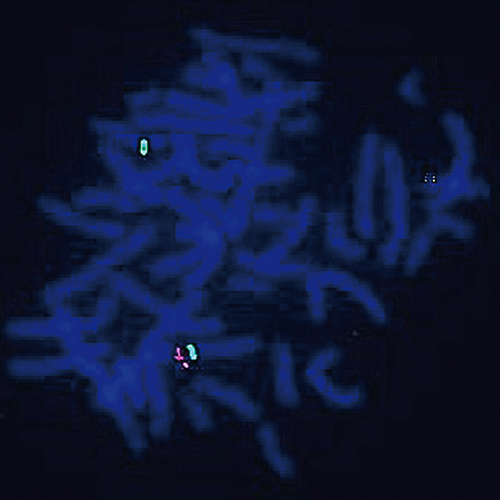

CDKN2A (9p21) / 9q21 hybridized to a metaphase spread showing a normal pattern (2R2G).

Hemizygous deletions and rearrangements of chromosome 9, band p21 are among the most frequent cytogenetic abnormalities detected in pediatric acute lymphoblastic leukemia (ALL). This deletion includes loss of the CDKN2A (previously known as p16, INK4A or MTS1) / CDKN2B (previously known as p15, INK4B or MTS2) genes, which are cell cycle kinase inhibitors and important in leukemogenesis. The CDKN2A (9p21) specific FISH probe is optimized to detect copy numbers of the CDKN2A gene region at region 9p21. The 9q21 region probe is included to facilitate chromosome identification.